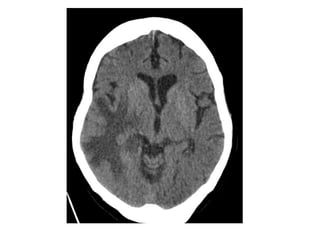

CT and T2W-gradient echo image of a hemorrhagic infarction

limited to the territory of the lateral lenticulostriate arteries